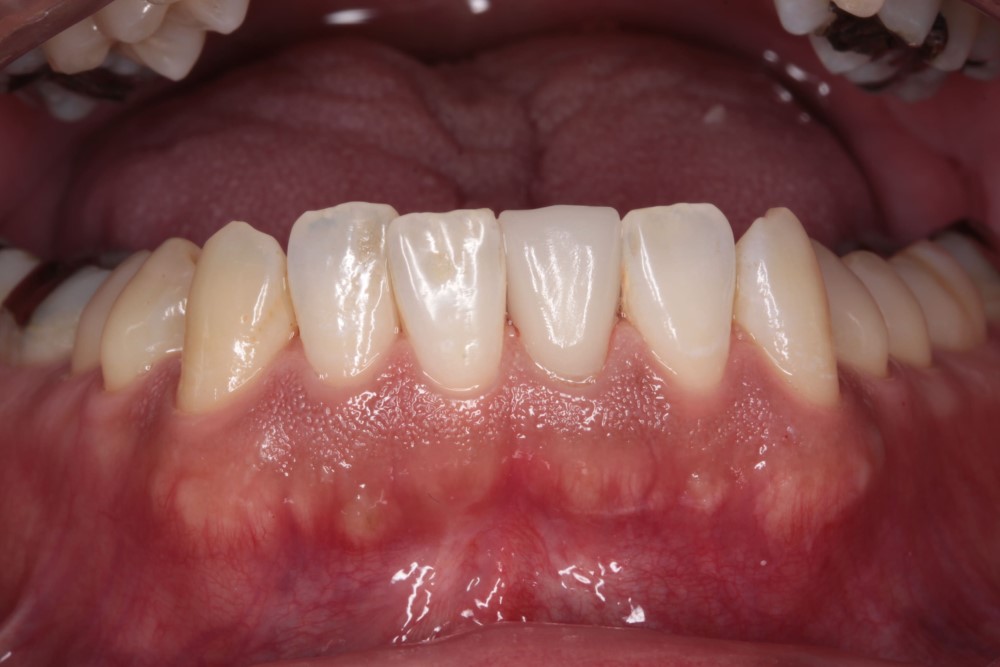

キレイな歯とキレイな口元で思いっきり笑おう!

笑ったときにちらりと覗く銀歯、気になりますよね。セレックのセラミック治療なら歯の見た目を美しくし、なおかつ健康なお口にするための治療です。歯の印象は、あなたの印象に深くかかわります。ぜひセレックのセラミック治療で健康で快適な毎日を手に入れてください。